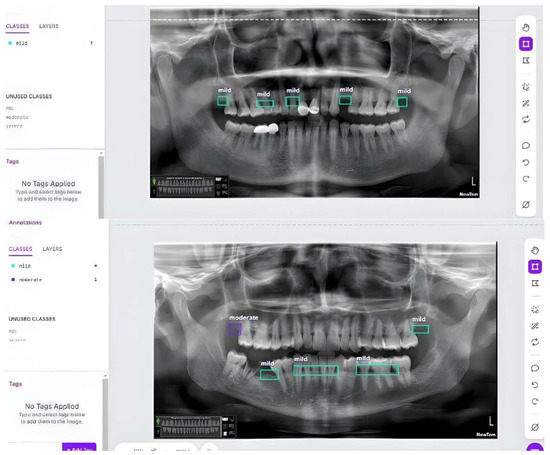

3.3. Results of the Secondary Model (YOLOv8)

4.2.2. The Secondary Model (YOLOv8)